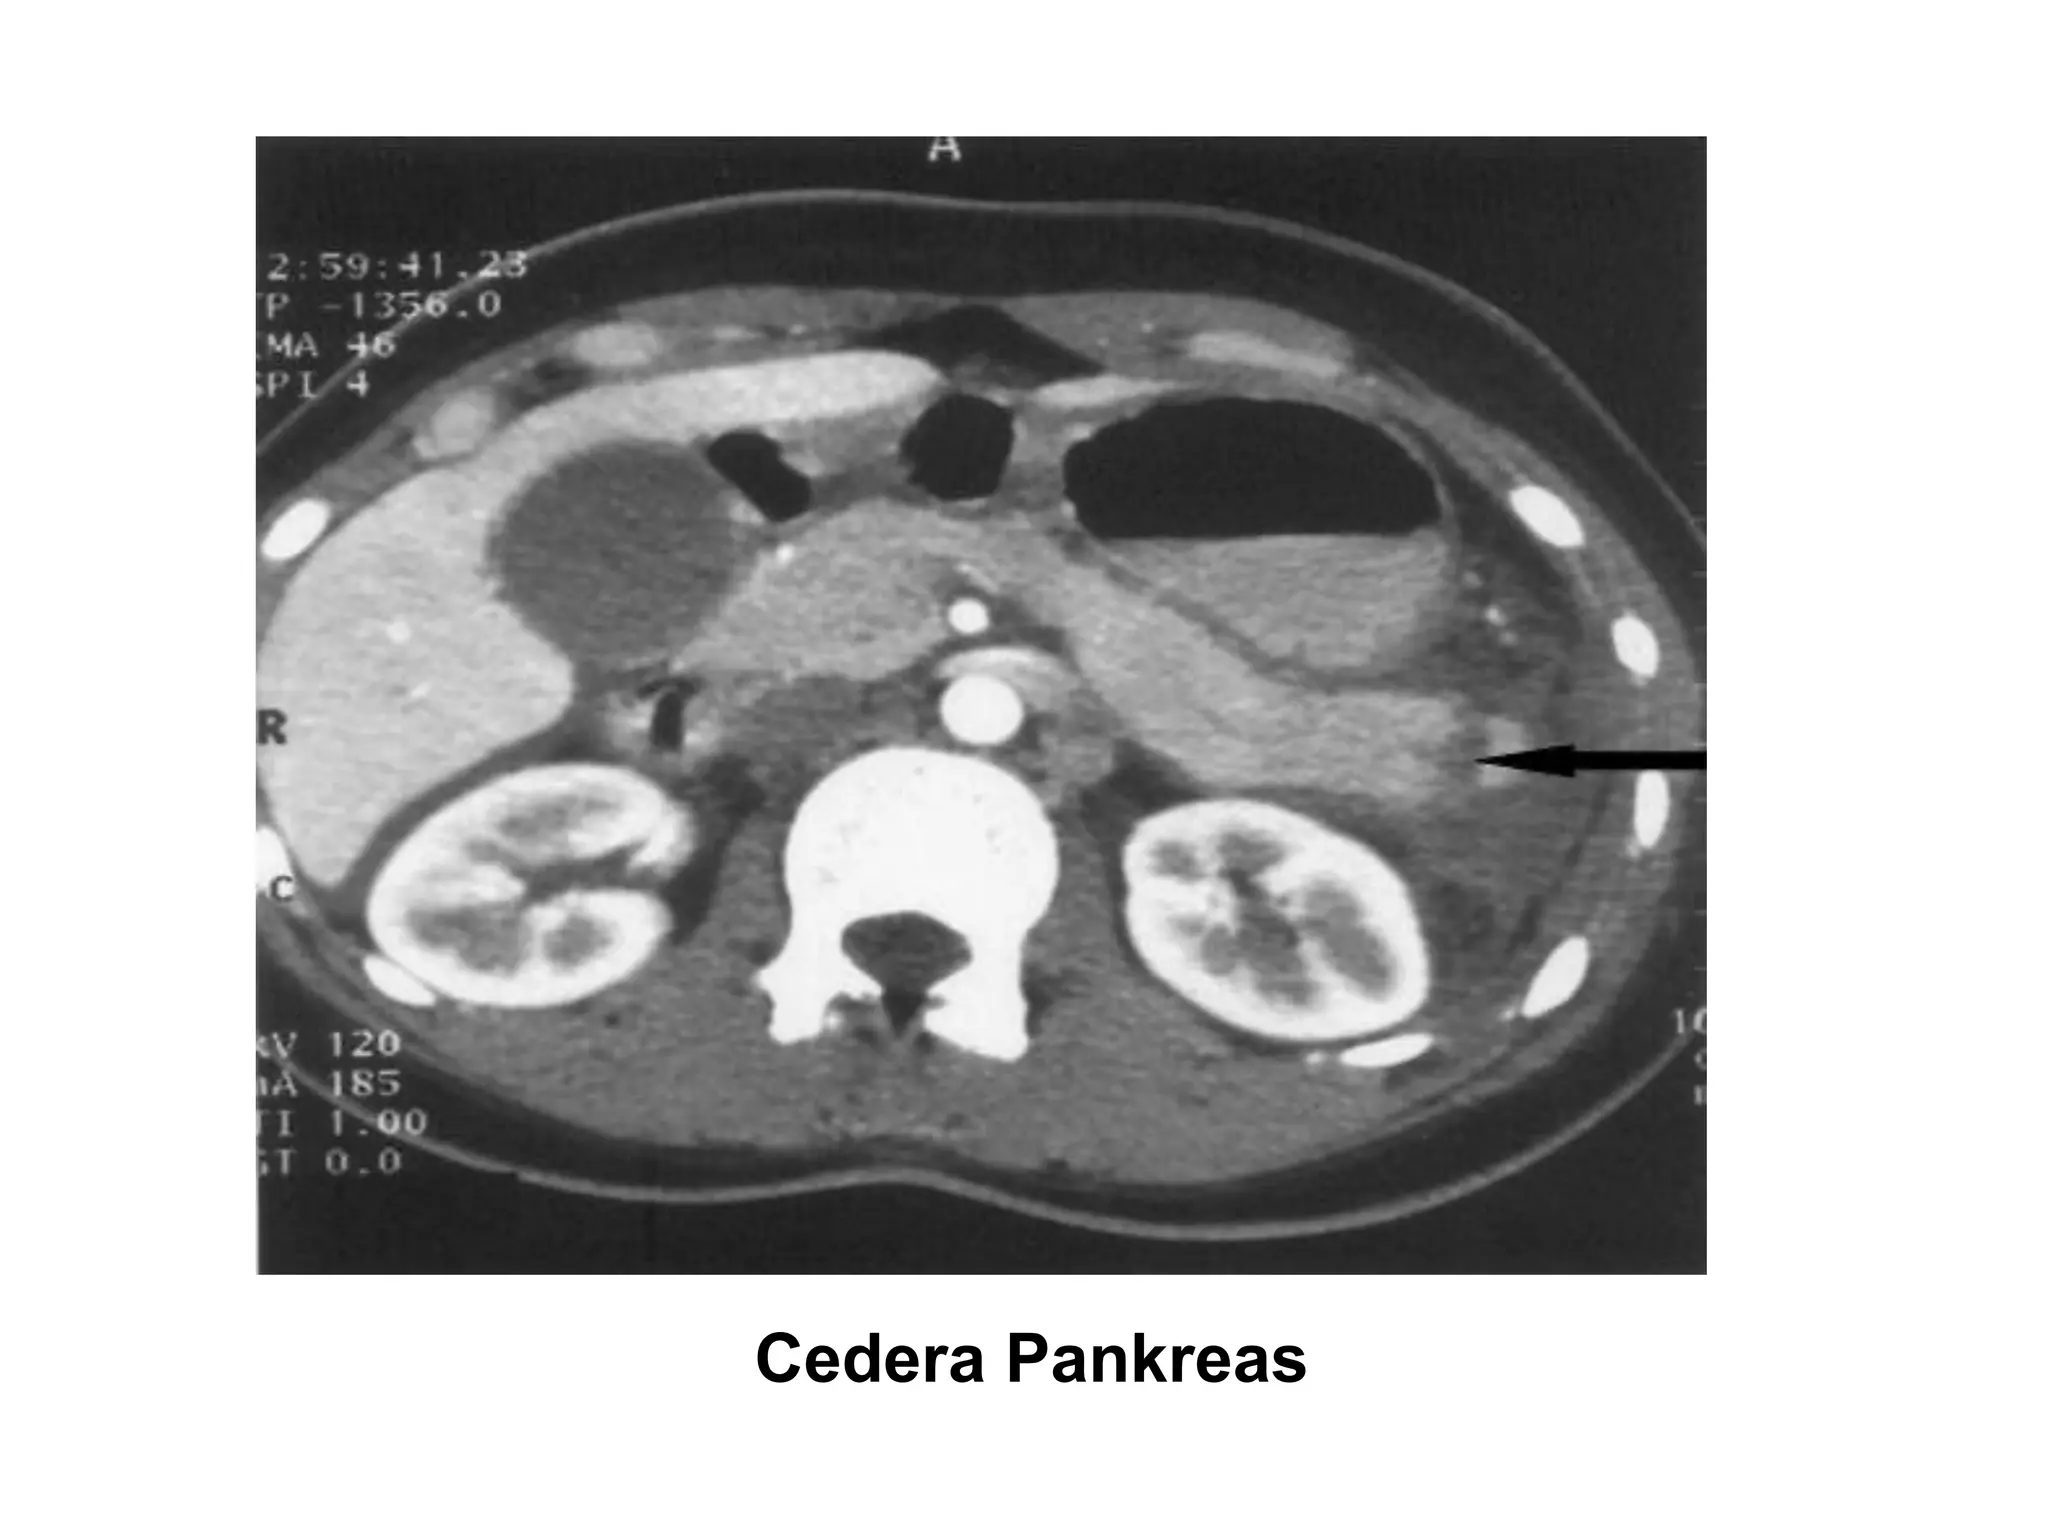

Early unenhanced CT was a good indicator

of severity of acute pancreatitis

Warko Karnadihardja, Bandung 2005

Cedera Pankreas